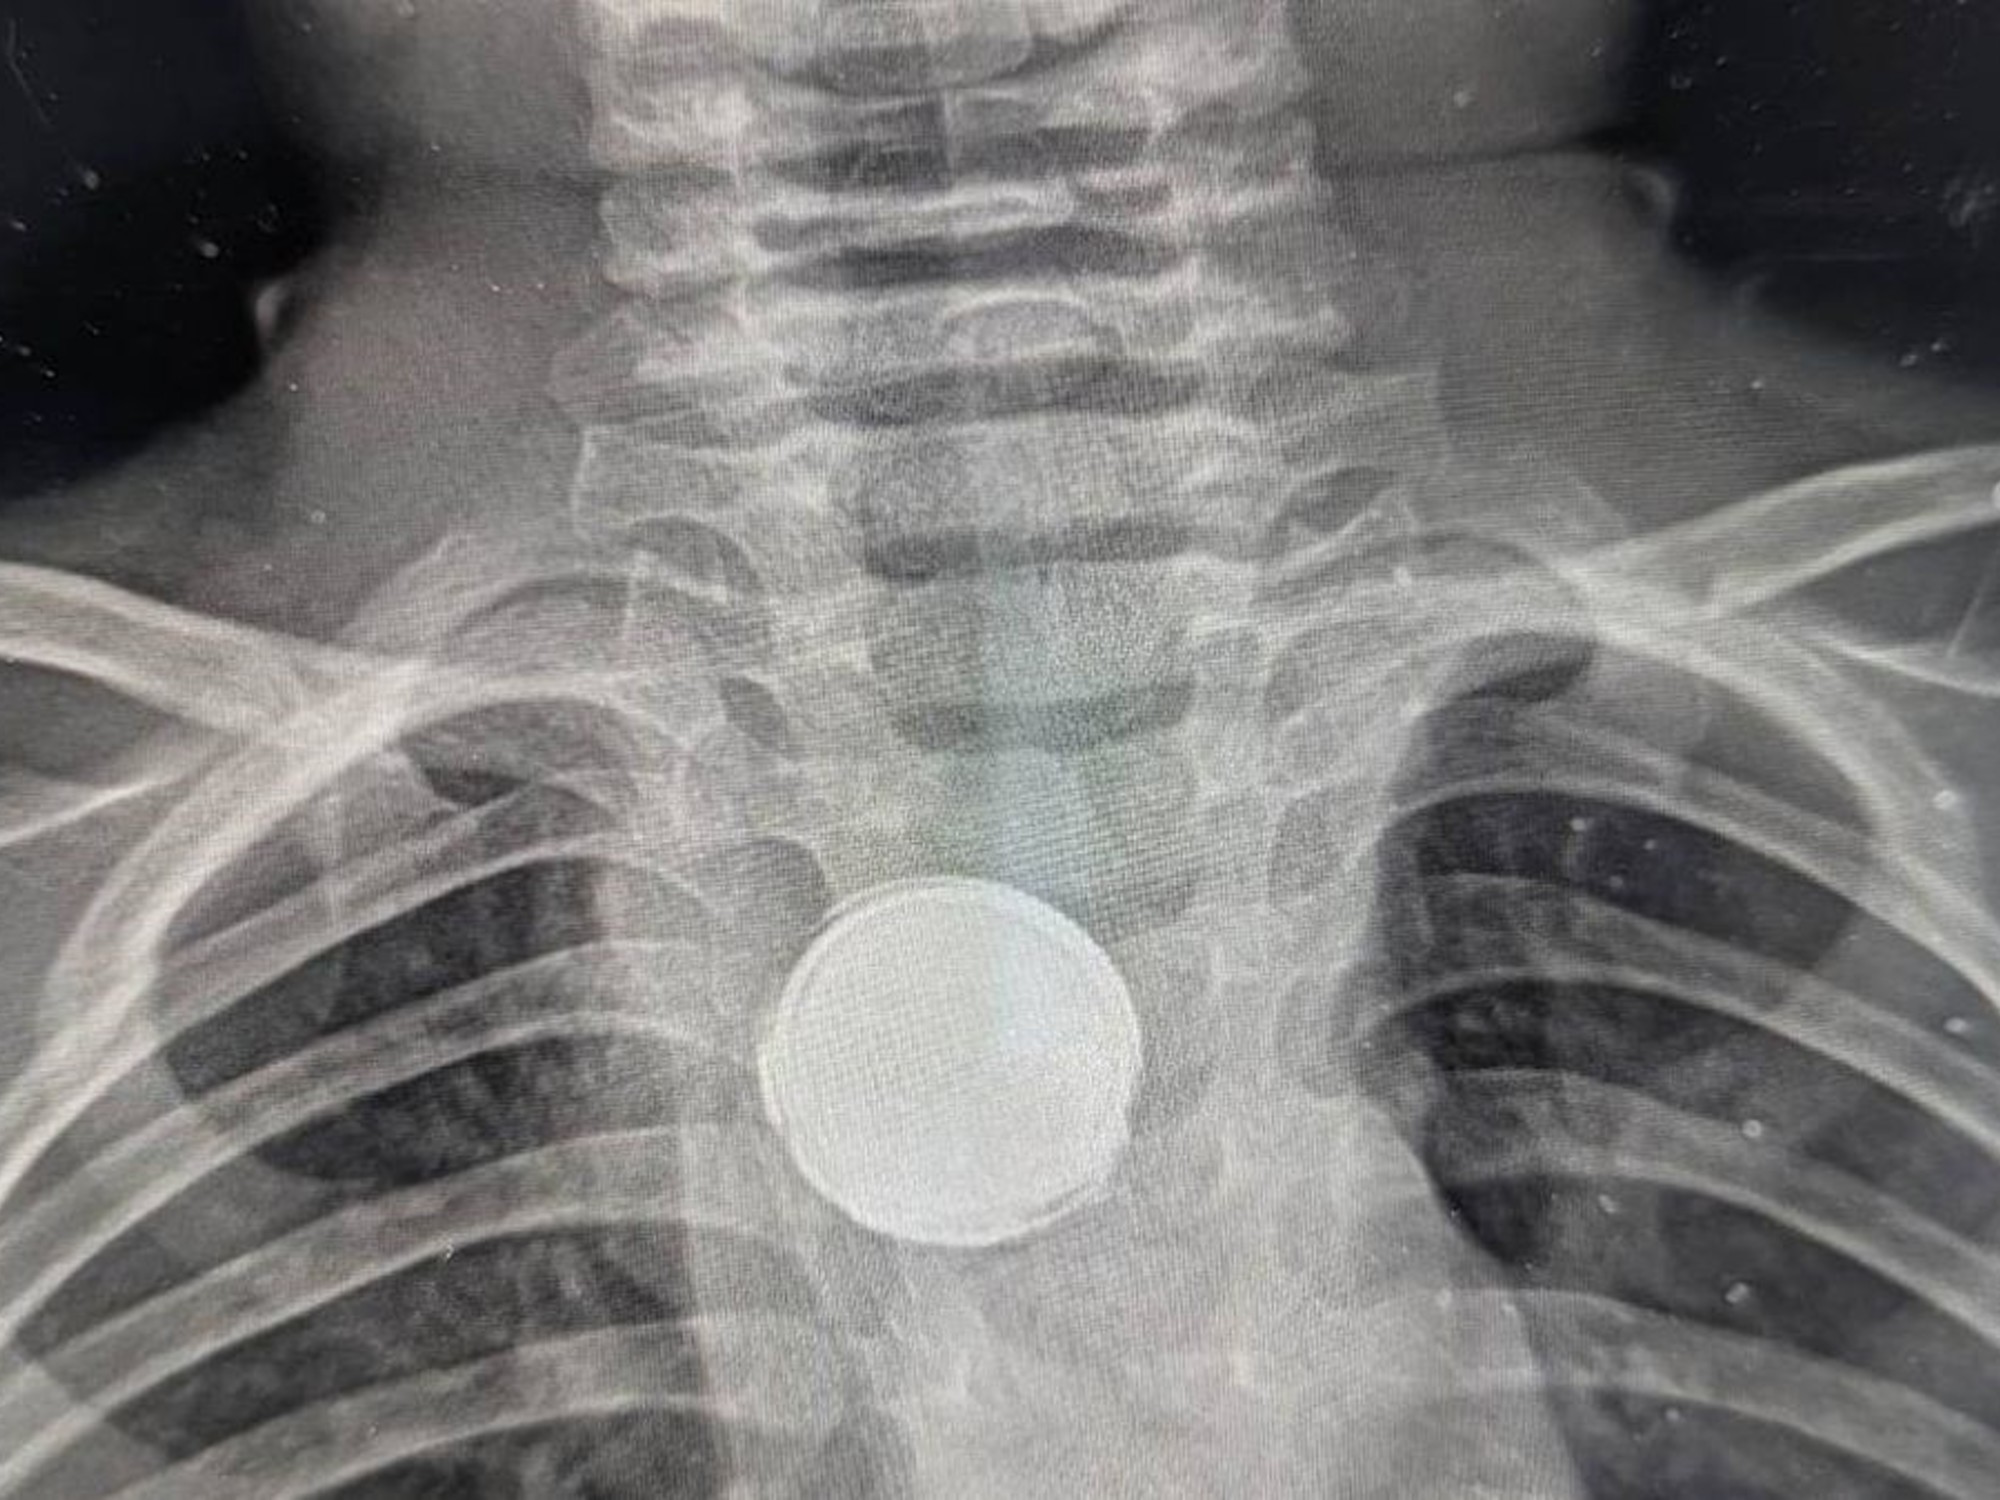

Bebé de 11 meses se traga una

April 9, 2026Alejandra OropezaChiapas,Noticias,Seguridad#FGE,#seguridad,ChiapasMomentos de tensión y desesperación vivió una familia en Tuxtla...